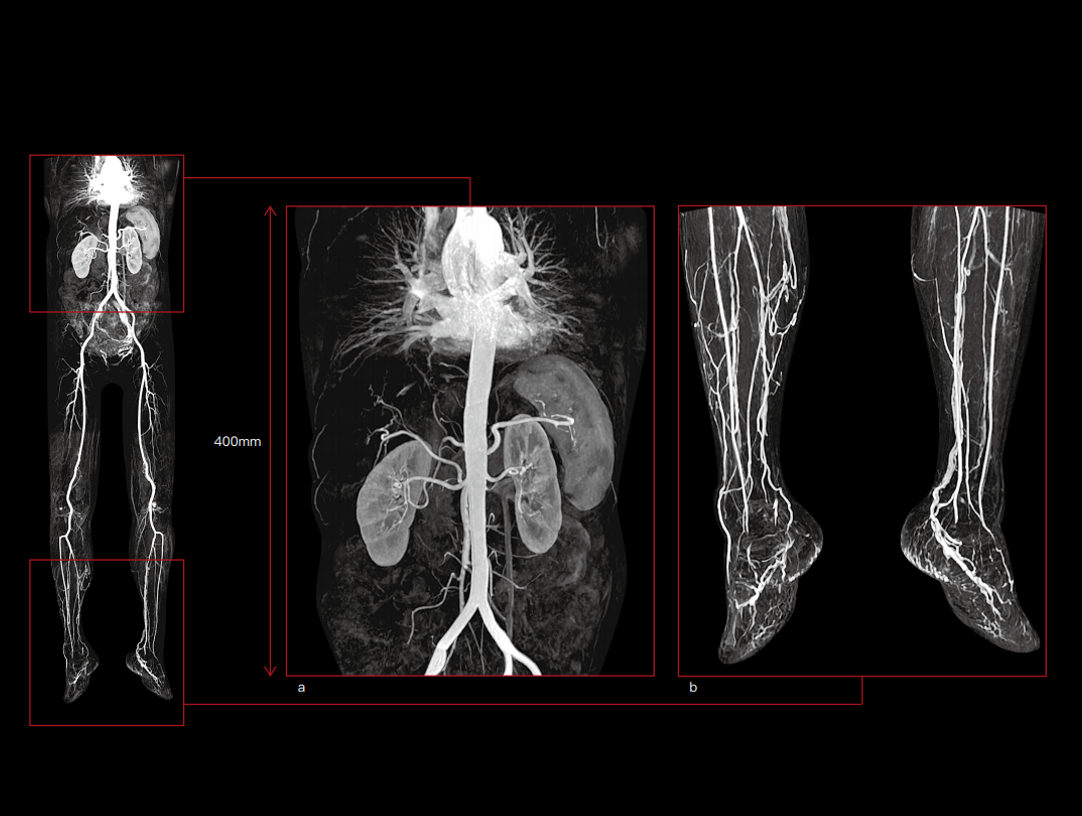

Wysokie parametry gradientu poprawiają szybkość pozyskiwania danych i skanowania, co pozwala zwiększyć wydajność pracy.

Potężny magnes 3,0 T ma krótką konstrukcję (170 cm), aby zapewnić wysoką jednorodność pola magnetycznego. Daje to solidne podstawy szybkiego obrazowania i doskonałego nasycenia tłuszczu w dużym polu widzenia, a także znakomitego obrazowania poza centrum.